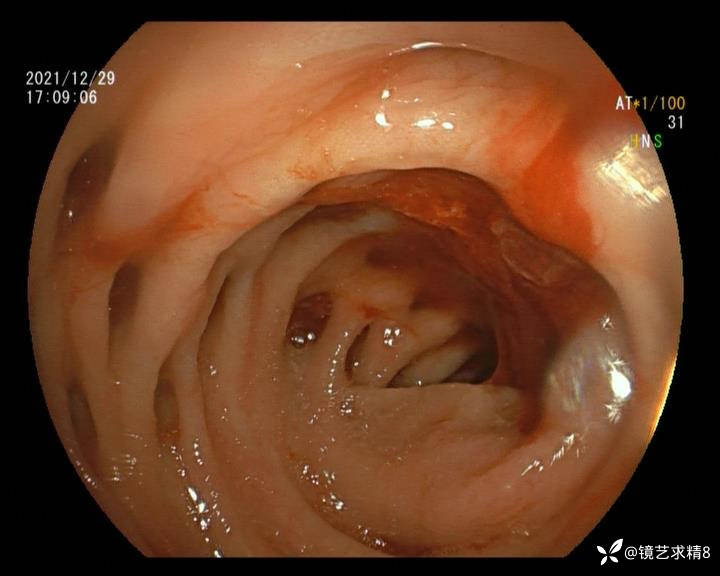

患者以消化道出血入院,胃镜未见异常,肠镜进入乙状结肠就看到很多憩室,同时还看到肠腔用清肠药后移动下来1枚尖锐的枣核,这么多憩室,这个枣核扎入憩室的机会非常大,推测应该是掉入一坑🕳就算出来还会有很多坑🕳🕳🕳等着,掉入憩室内很容易刺破血管,这可能就是消化道出血的原因,继续前进可以看到有一些憩室内翻,还有一些息肉,问题来了,那么多憩室,犯罪分子是抓住了,它在那些憩室内作过案?到达回盲部后挨个冲洗,但憩室大小又不足以把镜头进入憩室内观察,针对有血块的憩室冲洗后可疑出血的以夹子闭合或套扎,取出枣核,如果有锥形透明帽可能钻入憩室精准电凝效果更好,若内镜下操作失败介入治疗成功率更高,经内镜下治疗后观察未再出血出院。